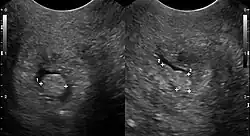

| Cervical polyp on ultrasound | |

Cervical polyps can be seen during a pelvic examination as red or purple projections from the cervical canal.[4] Diagnosis can be confirmed by a cervical biopsy which will reveal the nature of the cells present.[4]

- ^ a b c Bates, Jane (1997). Practical Gynaecological Ultrasound. Cambridge University Press. p. 77. ISBN 1-900151-51-0.